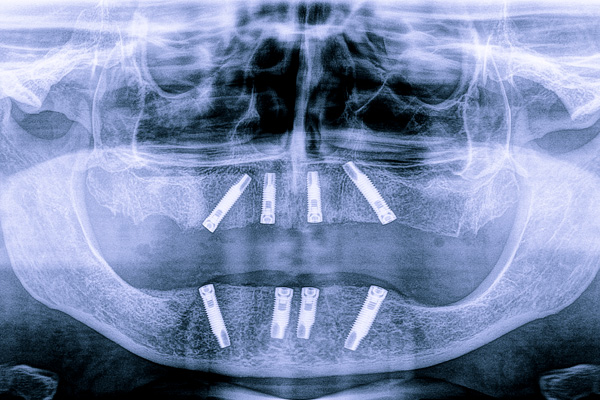

Ortopanoramica digitale in HD — e TAC Cone Beam 3D se necessario

Non una radiografia di routine. Una mappa digitale completa della sua bocca, in alta definizione, che permette di vedere con precisione la struttura ossea, la posizione dei denti, eventuali infezioni o problemi non visibili a occhio nudo. Nei casi che lo richiedono, integriamo con una lastra tridimensionale Cone Beam, lo standard diagnostico più avanzato disponibile oggi in odontoiatria.

Accoglienza, ortopanoramica digitale, visita con il Dr. Schmitz, consulenza finanziaria, preventivo scritto.

La prima visita da FreeSmile è un’analisi completa del suo caso e include l’ortopanoramica digitale HD, la visita con il Dr. Schmitz con check-up parodontale e oncologico, la consulenza finanziaria e il preventivo scritto. Non esistono costi aggiuntivi non comunicati preventivamente: la trasparenza è un principio fondante del nostro studio.

La prima visita ha una durata di circa 60 minuti. Il tempo è strutturato in tre fasi: diagnostica strumentale (radiografie), visita clinica approfondita con il Dr. Schmitz, e fase finale con il Consulente Finanziario per la presentazione del preventivo e delle opzioni di pagamento.